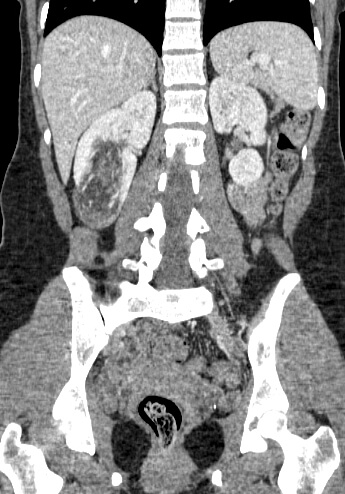

32 year old female who presents with an incidentally discovered right renal angiomyolipoma and undergoes prophylactic embolization.

Comment: This case demonstrates the classic appearance of an angiomyolipoma on CT and the hypervascularity associated with this benign tumor. The clearly seen abnormal vasculature enabled selective catheterization of the dominant supply to the angiomyolipoma and subsequent selective embolization with PVA particles. Embolization can be performed successfully with several types of particulate and/or liquid embolic agents. In this case, PVA was used successfully and no growth or viability has been seen on follow-up imaging after this procedure.